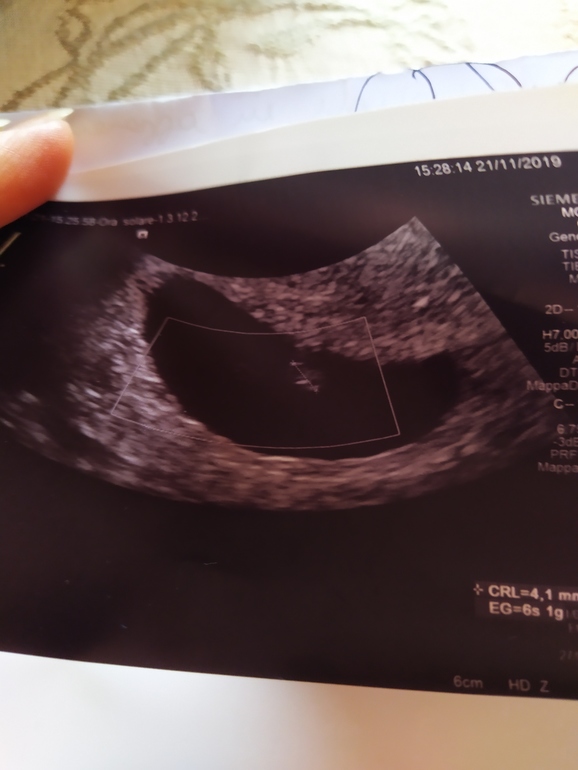

Девочки специально взяла выходной что бы поехать в больницу что бы сделать МА . У меня зб на сроке 6 нед а сегодня ровно 9 нед. Приехала прождала три часа и мне делают ещё раз УЗИ и говорят,у нас так не работает вы не можете сегодня сделать МА,так как у них берется напровление в определенный день и это может быть через неделю а может даже через две. Я им извените меня конечно же,но я как три дня отменила поддержку 600 в день и у меня может начаться в любой момент выкидыш и что мне делать тогда? На что мне ответили мы тебе дадим на 2 декабря и если начнется раньше ну и хорошо возможно все выйдет и само, главное следи за тт и головокружением и если что то к нам на чистку. Я просто в шоке,это вообще нормально?  вот мое последнее УЗИ,по которому она сказала на таком сроке выйдет как обычные мес

вот мое последнее УЗИ,по которому она сказала на таком сроке выйдет как обычные мес